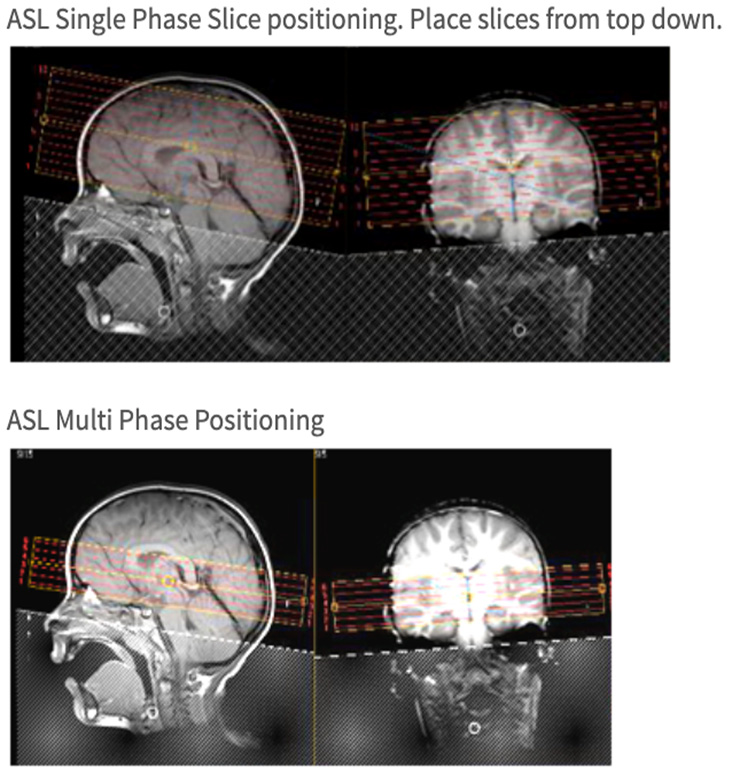

| AXIAL | ASL Single Phase | FFE EPI | 6 | 1 | no | 23 | no | Place from top down. Don't send raw data to PACS. |

| AXIAL | ASL Multi Phase | FFE EPI | 6 | 1 | no | 23 | no | See screen capture for slice placement. Archive raw data to DVD. |